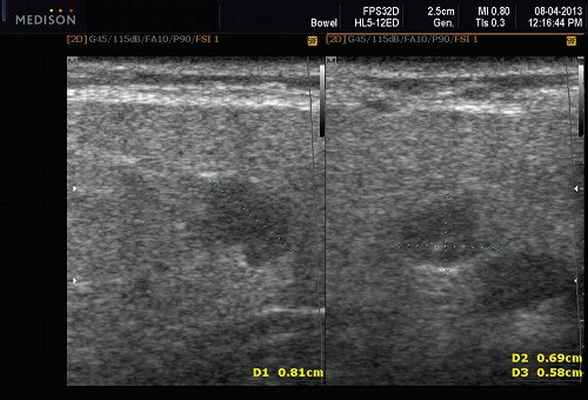

Рис. 3. Сиаладенит правой поднижнечелюстной слюнной железы.

Сиаладениты - большая группа полиэтиологических воспалительных заболеваний СЖ (рис. 3). Первичные сиаладениты - сиаладениты, рассматриваемые в качестве самостоятельных заболеваний (например, эпидемический паротит). Вторичные сиаладениты - сиаладениты, являющиеся осложнениями или проявлениями других заболеваний (например, сиаладенит при гриппе). Эхографическая картина при разной этиологии малоспецифична. Этиология имеет клиническое значение в процессе определения тактики лечения.